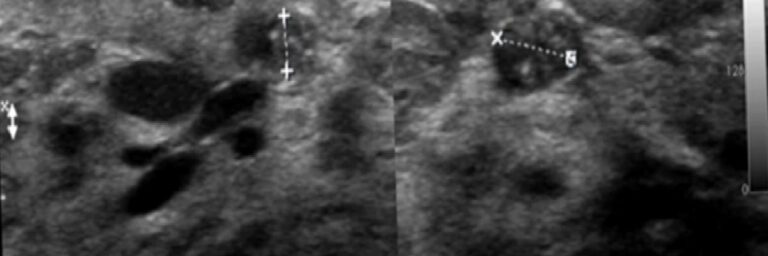

Fibroadenom kadınlarda her yaşta en sık rastladığımız “iyi huylu” meme kitlesidir. Sıklıkla her iki memede ve birden fazla sayıda bulunur. Memede radyolojik olarak “iyi huylu” olduğunu düşündüğümüz “solid” (hücre içerikli) kitlelerin çoğu fibroadenomdur.

Elbette tarama amaçlı muayenelerimizde daha önceden bildiğimiz kitlelerin durumunu da inceleriz. Bir kitlenin “iyi huylu” olduğundan emin olsak bile “şüpheli” herhangi bir yeni bulgu taşıyıp taşımadığına bakmak zorundayız: kitlenin şeklinde, kenarlarının düzeninde, iç yapısında, damarlanma özelliklerinde ve boyutlarında eskiye göre anlamlı bir farklılık var mı? Bu süreci tek bir radyologla götürmeyi tercih etmeli ve radyoloğunuzu özenle seçmelisiniz çünkü radyologların aynı vakadaki yorumları birbirinden farklı olabilir.

Radyoloğun yorum ve önerileri kaderinizi etkiler! Bir fibroadenomda yeni bulgular ortaya çıkması son derece istisnai bir durumdur ama varsa önemli olabilir ve biyopsiyi gerektirebilir. Yine de bu biyopsilerin çoğunda kanser çıkmaz. Fibroadenomların 10.000’de 2′ sinde kanser başlayabilir ama bu ihtimal, memenizin herhangi bir yerinde kanser başlaması ihtimalinden daha yüksek değildir. Üstelik bu kanserin, memenizin başka bir yerindeki yeni bir kanserden fazlası yoktur, genellikle azı vardır. Fibroadenomların içinde başlayan kanseröz değişikliklerin %90’ı in situ lobuler yada in situ duktal tiptedir ve gerçek anlamda kanser bile değildir; sadece kanser gelişimi için “yüksek risk” anlamı taşır. Bu değişiklikler memeden herhangi bir nedenle alınan parçalarda çok sık rastlanan ama sadece mikroskopla görülebilen (elle yada gözle seçilemeyen) “tesadüfi” patolojik bulgulardır. Kanser dışı nedenlerden ölen ve otopsi yapılan kadınların memelerinde bunlara çok sık rastlanır; kısacası önemsizdir! Meme kanseri taramalarınız düzenli ve kaliteliyse ve belli bir meme radyoloğunun takibindeyseniz bu kanserin de en erken evrede (Evre 0 yada1) yakalanması çok kolaydır. Türkiye’de taramalara rağmen meme kanserleri genellikle bu kadar erken evrelerde bulunamamakta, diğer yandan her yıl yüzbinlerce kadın gerçek dışı gerekçelerle gereksiz yere ameliyat edilmektedir.